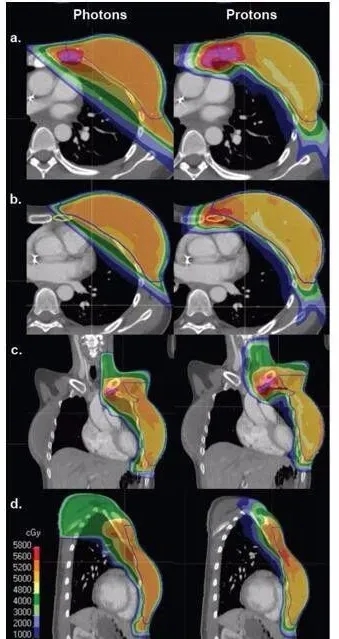

1左侧为光子治疗,右侧为质子治疗。光子治疗的内乳淋巴结和深部胸部的覆盖率受到心脏和肺照射剂量的限制。

(a)左乳内淋巴结增强区的等剂量云;(b)下乳内淋巴结区的等剂量云;(c)锁骨上区累积剂量为45.0 Gy;(d)左乳累积剂量为50.4 Gy,内乳淋巴结增强区累积剂量为57.6 Gy。

左图显示了与 X 射线或光子疗法相比,质子疗法治疗晚期乳腺癌期间身体接受的辐射量。颜色表示接受辐射的身体区域。与 X 射线相比,质子治疗显著降低了对心脏和周围健康组织的辐射剂量。

图 传统光子疗法(左)与质子疗法(右)的放射范围对比